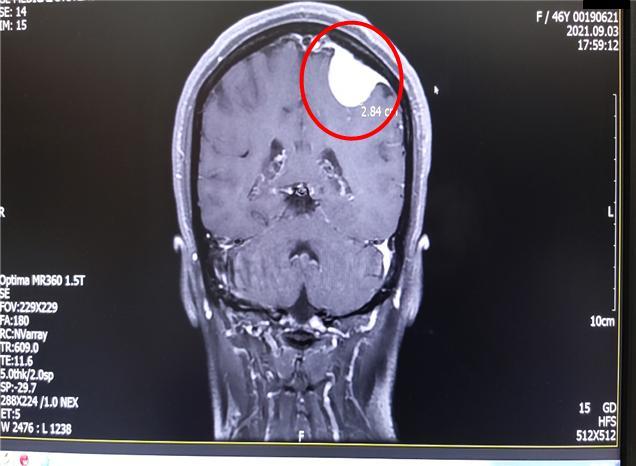

뇌 CT 사진을 보여주는데 두개골 안에 하얀 동그라미가 제법 큼지막하게 보인다.

“뇌 CT 상에 뭔가 보여요. 자세한 거 알아보셔야 하니 뇌 MRI 찍어보시죠. 제가 바로 신경외과에 예약 잡아 드릴게요"

야간 수술을 마친 신경외과 원장을 간신히 만나 설명을 들을 수 있었다. 뇌 MRI 검사 결과도 CT 사진과 동일하다고, 하얀 부분이 종양이라고 했다. 크기도 3cm가 넘어 보인다고. 수술을 해야 한다고 했다.

’ 종양‘ 처음 듣는 말 같다. 머리가 하얘지면서 물었다.

”내 머릿속에 암이 있다는 말인가요? “

뇌mri.jpg